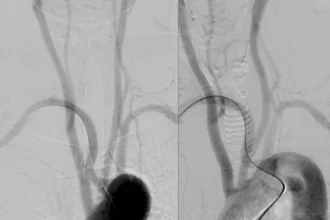

An executed pericardiocentesis procedure helped drain approximately 1 liter of bloody fluid, which, upon scrutiny, indicated malignancy, indicative of adenocarcinoma. Computed tomography scans of chest and abdomen revealed a pericardial effusion, pleural effusion on both sides and numerous hypodense liver lesions (Figure 1B).

Figure 1 encapsulates the significant diagnostic findings: (A) ECG depicting the characteristic trio of symptoms for cardiac tamponade – sinus tachycardia, weak QRS voltages and electrical alternans (pointed out using arrows). (B) CT scan exposes pericardial effusion with the pericardiocentesis catheter neatly in place (marked using an arrow), and bilateral pleural effusion. Click to open in a new tab, or download for more detailed examination.